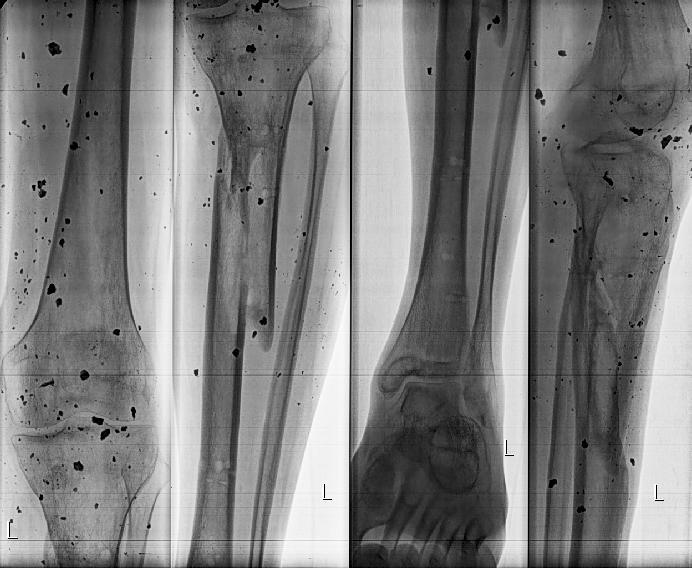

Деформации после минно-взрывного ранения.

Как лучше устранить деформацию обеих голеней.

Уважаемые коллеги на лечение спустя 10 мес. после травмы поступил 35 летний пациент. Изначально лечился в аппаратах. Длительно, в выписке описываются инфекционные осложнения. В настоящее время аппараты демонтированы, ран на правой и левой голени нет.

Слева планируем устранить в один прием с фиксацией стержнем.

Справа - мнения разошлись: от тоже стержнем, до остеотомии в нижней трети (вне перелома) с коррекцией механической оси.